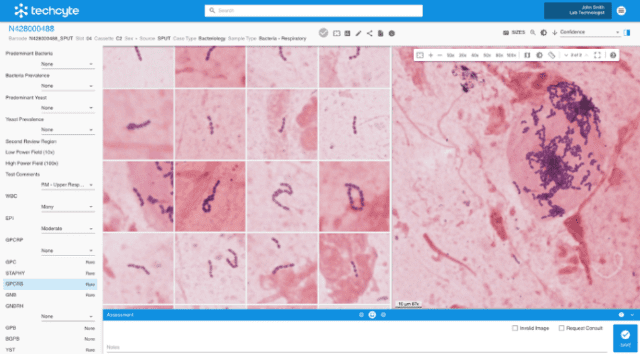

Built with pathologists to deliver an ultrafast cloud-based viewer, flexible worklist, integrated workflows, and state-of-the-art AI.

Techcyte Fusion: The unified anatomic and clinical pathology AI platform

What to expect from the Techcyte platform